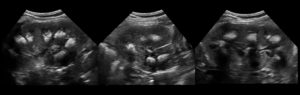

При патологиях сосочки пирамид уплотняются, могут покрыться кристаллами солей или деформироваться. Эхогенность почки при этом возрастает. На экране же появятся светлые пятна, увеличится контрастность. Это явление получило название синдром выделяющихся пирамидок.

Метод УЗ-исследования основан на степени отражения ультразвука от тканей различной плотности. Гиперэхогенность – это усиление акустической тени, то есть на практике это значит, что структура органа имеет высокую плотность и хорошо отражает ультразвук. На мониторе это выглядит как более светлая, почти белая область.

Есть также такое понятие при УЗ исследовании почек, как синдром выделяющихся пирамидок. При этом повышается эхогенность коркового слоя и пирамидки выглядят заметно темнее, выделяются.

В норме эхогенность коры сравнима с паренхимой печени, ее повышение указывает на серьезное нарушение в работе почек. Это может быть острый гломерулонефрит, острая почечная недостаточность различной этиологии.

Например, при поражении почек отравляющими веществами.

У новорожденных детей и до 3-летнего возраста такой симптом считается нормой. Кора выглядит гиперэхогенной, поскольку количество нефронов в почке закладывается внутриутробно, корковый слой у плода еще недостаточно развит, поэтому плотность повышена. У новорожденных соотношение коркового и мозгового вещества составляет 1 к 5, а у взрослых 2 к 3.